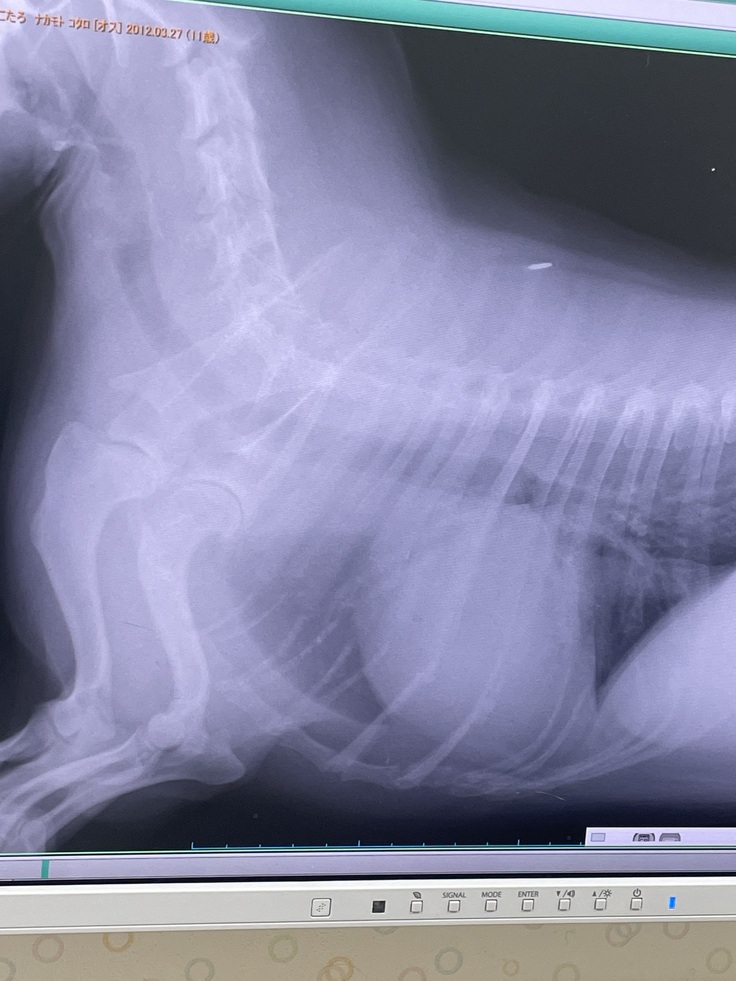

▼レントゲン

去年2月より心臓が大きくなっており肺・呼吸器が圧迫されていて咳が出る状態

(普通のわんこは真ん中に心臓があるが、こたろは左に寄っていて、

これが生まれつきなのかはわからないとの事)

※かかりつけ病院の診断書(病院名・住所は隠してあります。先生の掲載許可済み)